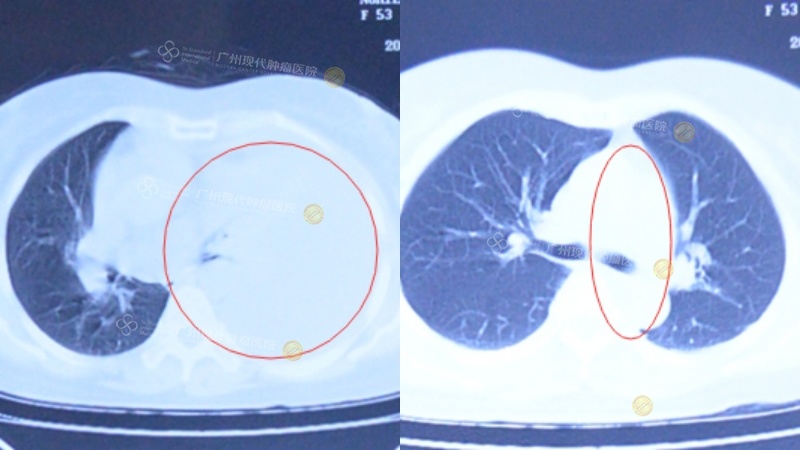

2014年9月,严女士确诊肺癌。在越南当地医院治疗无果后,来到广州现代肿瘤医院,入院检查确诊左肺低分化腺鳞癌,并伴有胸膜及纵膈淋巴结转移。经过整合微创介入治疗,病情明显好转。治疗结束至今,身体一直保持着良好的状态。现已成功抗癌11年。

(左)治疗前,白色为胸腔积液;(右)治疗后,胸腔积液消失